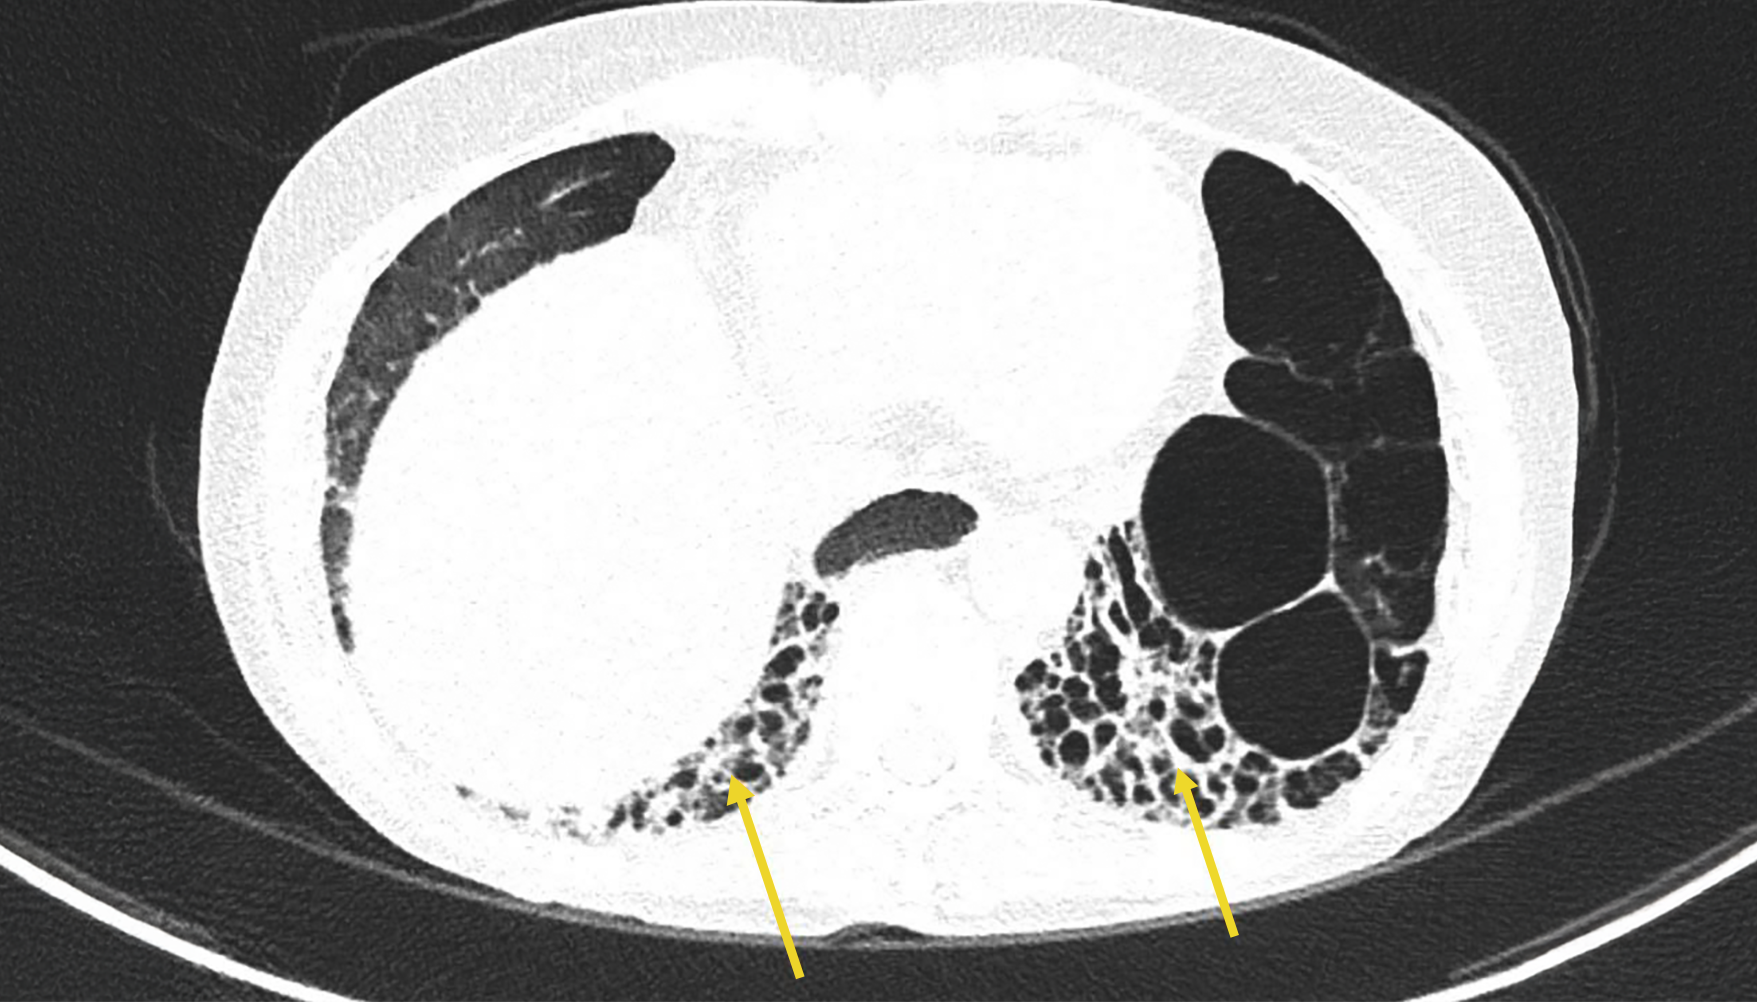

A CT scan of the lungs shows Ms. My has bronchiectasis, honeycomb interstitial lesions in both lung bases, and other damage. Tam Anh General Hospital |

A CT scan of the lungs shows Ms. My has bronchiectasis, honeycomb interstitial lesions in both lung bases, and other damage. Tam Anh General Hospital